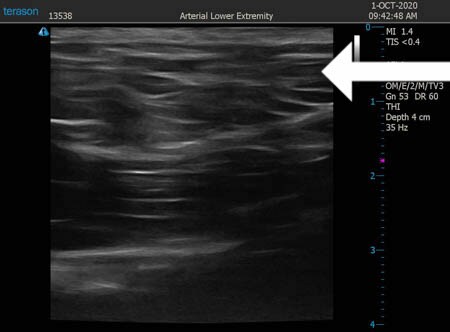

同様に右肩甲骨横 ↓ ↓ ↓

↓ ↓ ↓